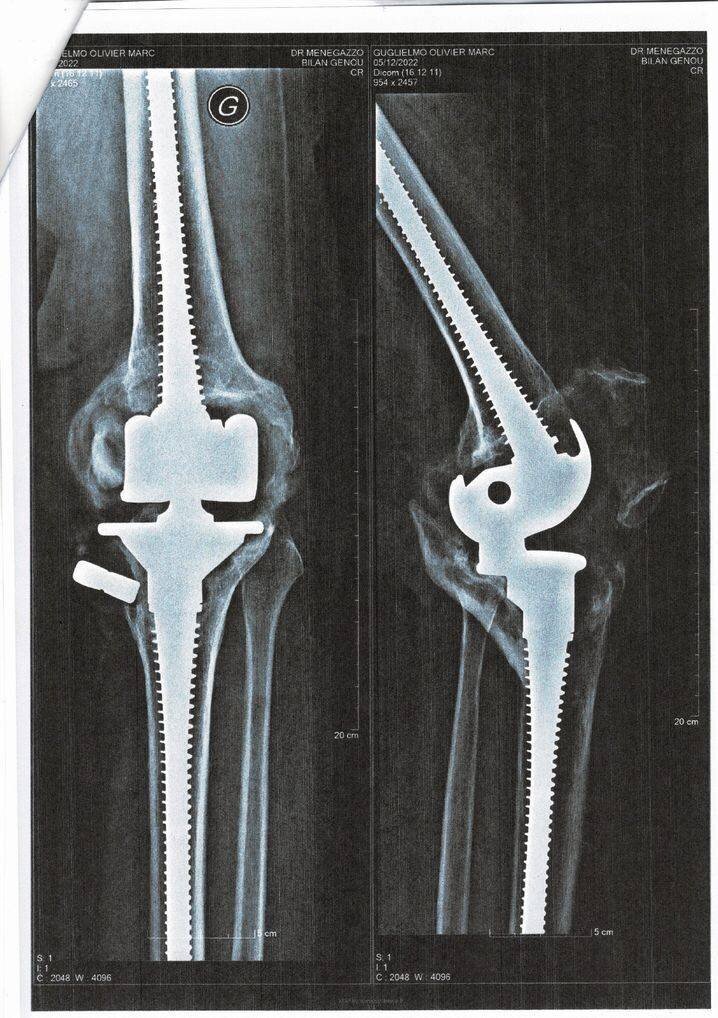

Olivier Guglielmo, 55 ans, d’origine azuréenne, partage un parcours similaire. Opéré à 17 ans par le Dr Bousquet après un accident, il a lui aussi dû remplacer à deux reprises les pièces de sa prothèse. Depuis fin 2023, il fait face au même blocage et refuse également l’amputation. Il alerte sur les risques, notamment la métallose due au frottement métal contre métal, qui peut endommager les tissus environnants.